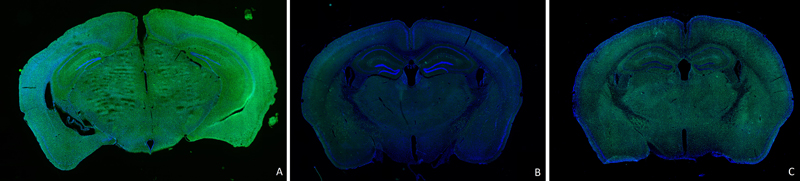

Microglia are abundant cellular constituents of the brain that play important roles in brain development, maintenance and the pathogenesis of most disease states. We are taught to consider microglia as playing a central role in virtually all nervous system repair processes, including that of TBI. Indeed, although the precise mechanism for their action remains unknown, microglia have been thought to mediate ongoing neuroinflammatory damage to the brain that is responsible for at least some of the long-term functional sequelae of TBI and even aspects of potential subsequent neurodegenerative phenomena. Recently, a series of drugs have been identified that inhibit colony-stimulating factor 1 receptor (CSF-1R), which microglia depend upon for their survival. These drugs penetrate the brain after oral administration and within two to three weeks are able to almost completely deplete the entire microglial cellular compartment of the brain in an exposed animal. Following withdrawal of the drug, there will be a steady repopulation of the brain by microglia (Figure 1). Importantly, the repopulated microglia appear to be a new rejuvenated population of cells without a prior history of antigen exposure. The primary agent used in such microglial repopulation experiments is referred to as Plexxikon (PLX) 5622.

Figure 1. Microglia are depicted in 8 weeks old CX3CR1-GFP mice (microglia – green; DAPI – blue) A) control mouse, normal diet, B) 3 weeks following a diet containing 1200 mg/kg of PLX5622 (note virtual complete absence of microglia) and C) after 3 weeks on the PLX5622 diet then 2 weeks on the control diet (note the return of prominent green staining from the repopulated microglia). From ongoing studies of K. Whiting and Z. Galdzicki of Uniformed Service University - Neurosciences Program.